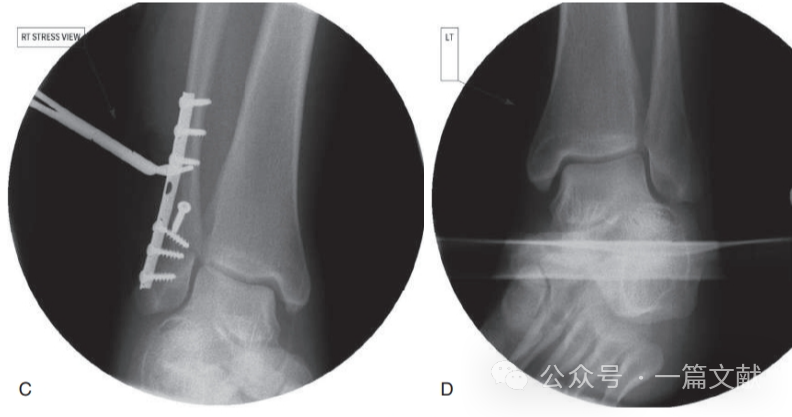

螺钉最终固定的踝穴位片与健侧相对比如下图:

图片